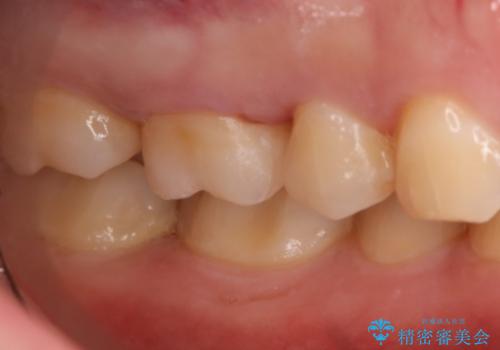

虫歯をしっかり治したい セラミックインレー

- 右上6番の虫歯治療を主訴に来院された患者様です。

切削量・形態を考慮し、セラミックインレーでの治療を計画しました。

保険の材料が劣化し中で虫歯が進行していたので、全て取り除いた上で形を整え型をとりインレーをセットしています。